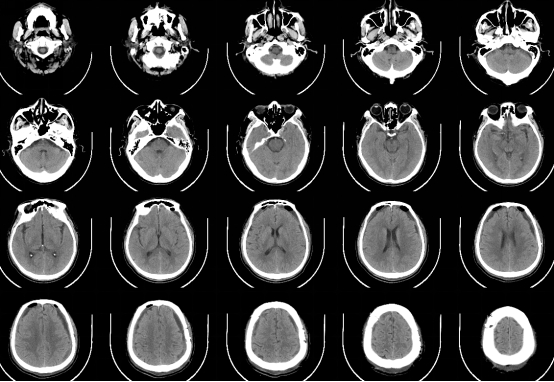

近期,我科完成了一例慢性硬膜下血肿手术。该患者男性,63岁,是因为“摔伤头部半年,记忆力下降,思维迟钝大约20天” 在当地医院就诊,行颅脑CT提示双侧额颞顶部慢性硬膜下血肿,脑疝,CT片可见慢性血肿有很多分隔。当地医院医生建议患者分二次行双侧开颅手术,清除硬膜下血肿,创伤很大,手术后需要住ICU,而且住院时间很长,费用高。患者家属犹豫不决,担心手术风险,于是带着CT片到我科门诊咨询。门诊孟主任阅片后告知家属,我科可以通过神经内镜微创手术治疗慢性硬膜下血肿,可以一次手术,手术创伤小,风险低,费用少,住院时间短,大约10天左右就可以出院,而且手术后不需要住ICU,于是家属当天下午就驱车带患者来我科住院。管床医生涂医生仅用一天时间就完成全部术前检查,第二天就安排了手术。手术中通过神经内镜观察到慢性硬膜下血肿有很多的分隔及纤维组织,与可自行流出的液态慢性血肿相比,该患者需通过吸引器反复仔细吸除血肿分隔及纤维组织,同时反复盐水、双氧水冲洗,避免血肿残留及复发。手术过程很顺利,术后患者清醒,无任何神经功能障碍及并发症,手术后10天患者治愈出院,在后期随访观察中,未见慢性血肿复发。

术前当地医院CT